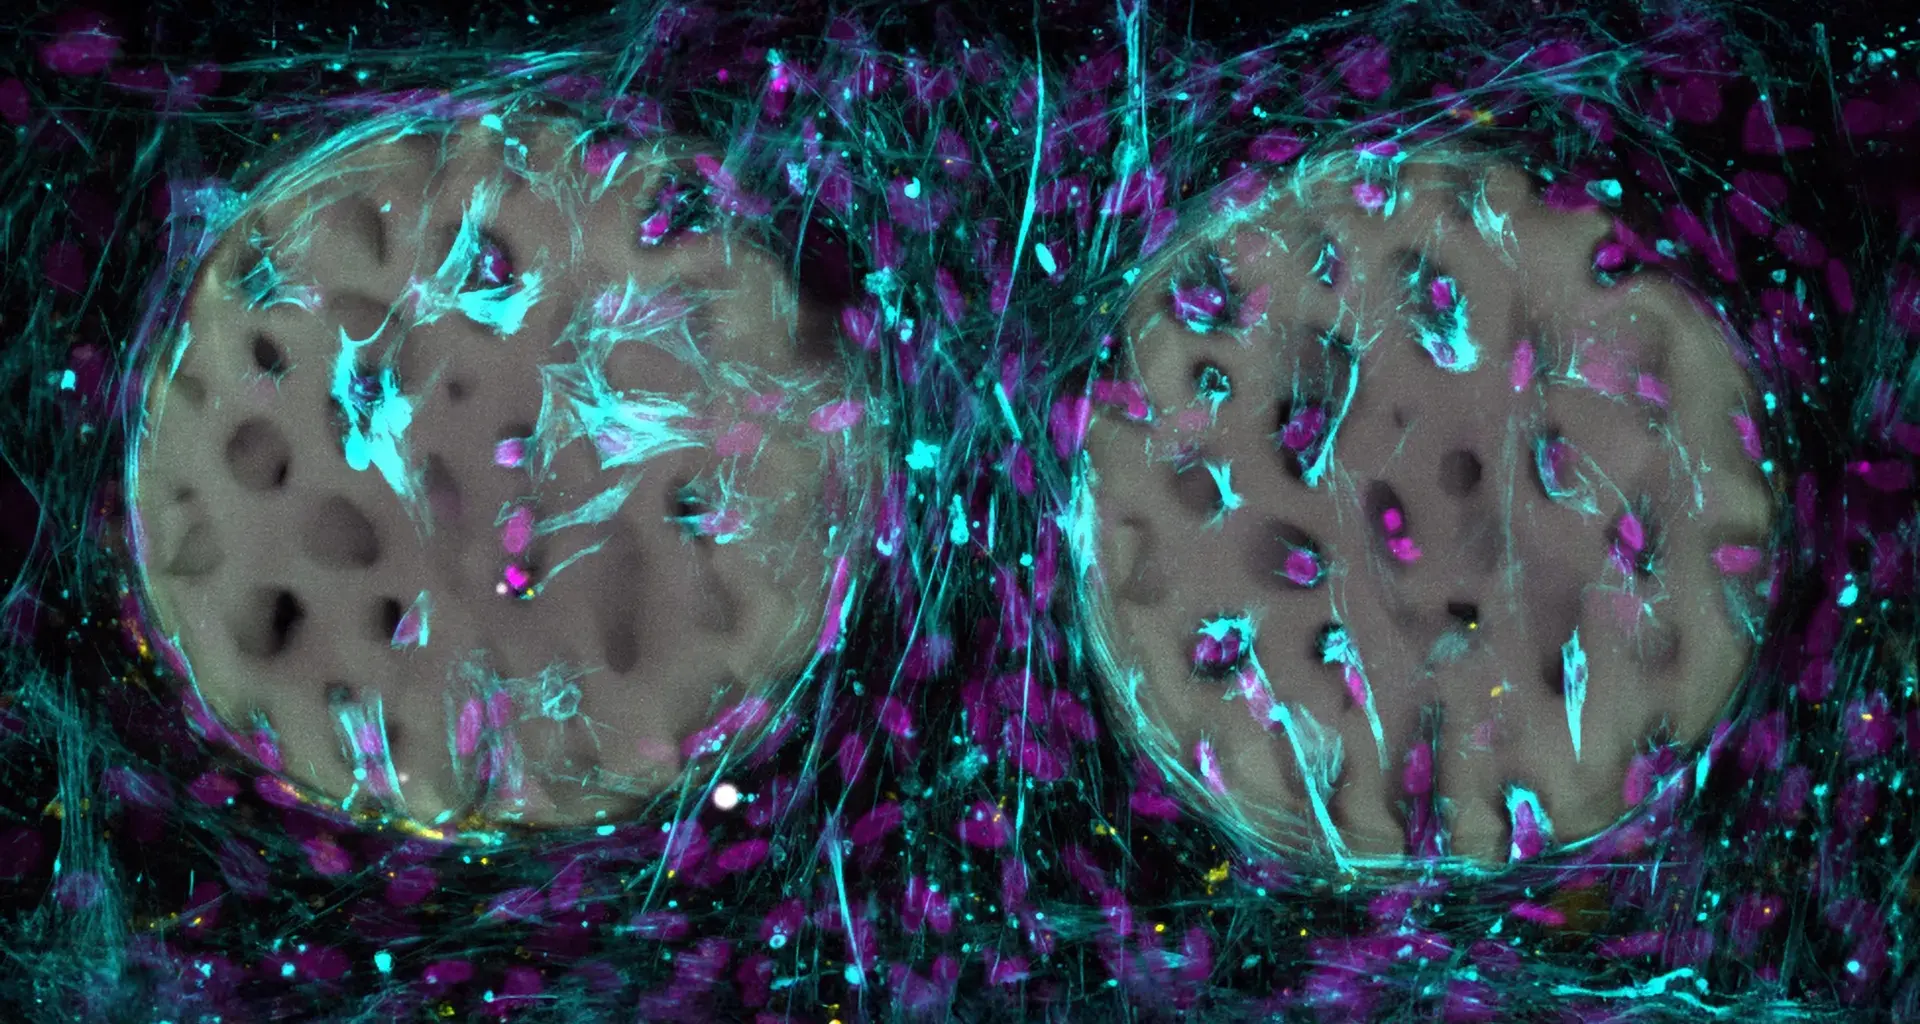

In their experiments, the researchers produced highly detailed hydrogel structures modeled on real bone. Using medical imaging as a guide, they recreated the delicate lattice known as trabeculae that gives bone its internal strength.

So far, the material has been evaluated only in laboratory experiments. In test tube studies, bone forming cells quickly moved into the structured hydrogel and began producing collagen, a key building block of bone. The researchers also confirmed that the material is biocompatible and does not harm these cells. The base material has been patented, and the team intends to make it available to medical manufacturers.